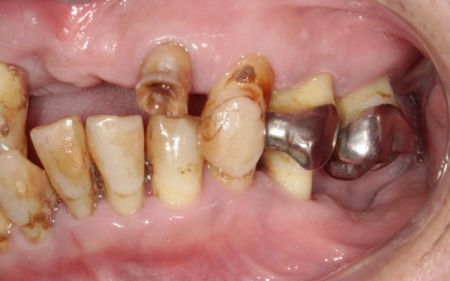

拝見したところ、患者様は上前歯が数本欠損しており、残っている歯を利用して橋渡しのように歯を補うブリッジ治療が行われていました。しかし、転倒による衝撃でブリッジが外れていました。

また、患者様は重度の歯周病によって歯を支える骨が減少し全体的に歯が揺れていました。

残っている上の歯7本(左右上側切歯、左右上犬歯、左右上第1小臼歯、左上第1大臼歯)と右下奥歯2本(第2大臼歯、第3大臼歯)は残すことが難しく抜歯が必要な状態です。